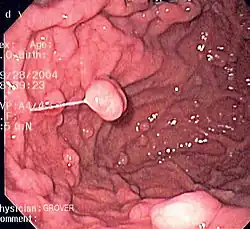

Clinical significance

Diseases

A series of radiographs can be used to examine the stomach for various disorders. This will often include the use of a barium swallow. Another method of examination of the stomach, is the use of an endoscope. A gastric emptying study is considered the gold standard to assess the gastric emptying rate.[50]

A large number of studies have indicated that most cases of peptic ulcers, and gastritis, in humans are caused by Helicobacter pylori infection, and an association has been seen with the development of stomach cancer.[51]